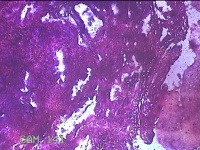

宫腔内容物

性别

女

年龄

37岁

临床诊断

异常子宫出血;女性盆腔炎

一般病史

阴道流血10天。

标本名称

大体所见

灰白暗红色不规则碎组织2.8x2.3x0.8cm一堆。

兄弟呀,这片子很难评价呀,是本身没固定好还是制片的问题?